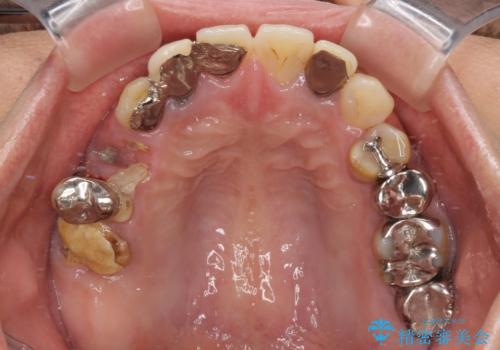

抜歯とむし歯治療を途中で放置 インプラント補綴治療